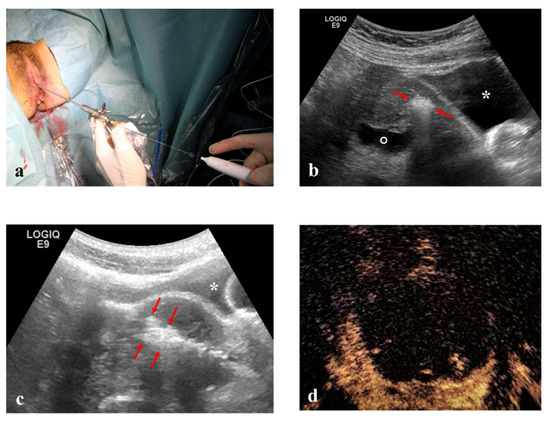

2.2. Instruments

This prospective study enrolled 54 consecutive patients. RFM was performed in three ways: Vaginal Ultrasound-guided RFM (VU-RFM), Laparoscopic RFM (L-RFM) and Hysteroscopic-RFM (H-RFM). These three methods of myolysis were performed both separately as an exclusive type of surgery and in a combined approach when the localization of the myomas required to use the same electrode through different access routes. The ablation device consisted of an RF energy generator (STARmed, VIVA RF generator VRS01, Gyeonggi-do, Korea 10355) and an electric pump for the continuous cooling of the electrode tip. The RF generator to which the electrode (STARmed Gyeonggi-do, Korea 10355) was connected simultaneously displayed the temperature of the electrode tip, the tissue impedance characteristics, the power and the ablation time. A 35 cm long 17G internally cooled electrode with an exposed tip of 10 mm or a variable exposed tip was used (Figure 1).

Pre-treatment evaluation was performed for all patients with conventional trans-abdominal and transvaginal (TV) ultrasound using an ultrasound machine equipped with a 3–5 MHz convex probe and a 1–6 MHz trans-vaginal probe (Logiq E9, GE Healthcare, Milwaukee, WI, USA). Contrast-enhanced ultrasound (CEUS) evaluation was also performed for all patients after the intra-venous injection of SonoVue micro-bubbles contrast (4.8 mL; Bracco, Milan) to evaluate the vascularity of myomas (Figure 1). The micro-bubble contrast agent was mixed with 5 mL of normal saline solution and was administered via rapid bolus into the median cubital vein, followed immediately by 5 mL of normal saline solution.

Immediately before ablation, all patients were subject to a US-guided core-needle biopsy of all fibroids to be treated by 18 Gauge Bard Max-Core disposable core biopsy instruments (#MC1820, Bard Limited Crawley, UK) (Figure 1). At least two biopsies were taken for each myoma, but the number of biopsies changed according to the size of the fibroid (one biopsy per centimeter of fibroid) so that all areas of the fibroid could be evaluated. All tissue samples were sent to the Institute of Pathology for routine analysis, and all samples were classified as representative by pathology.

Figure 1. (a) 35 cm long 17 Gauge radiofrequency electrode at the left of the table and an 18 gauge disposable core biopsy instrument at the right. (b) Contrast-enhanced ultrasound (CEUS) evaluation before radiofrequency ablation of a fibroid. (c) Hyperechogenic line within the myoma viewable during the biopsy (arrowheads). (d) CEUS evaluation after radiofrequency (RF) ablation demonstrates no residual contrast enhancement within the fibroid (asterisk).